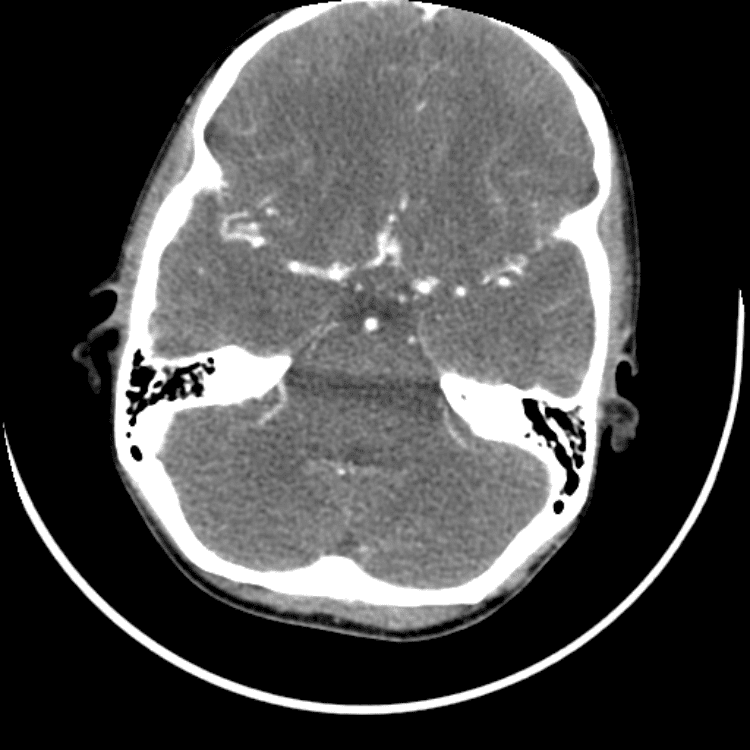

Head and Neck

Simulates call by including subtle or difficult cases and some normals.

27 cases